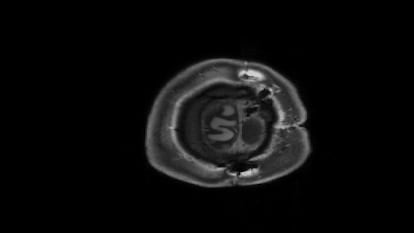

Estudiar a estas personas excepcionales puede ayudar a entender cómo funciona el cerebro más allá de la antigua imagen que relaciona regiones y capacidades. Esto es lo que ha hecho un equipo del Instituto Tecnológico de California (Caltech) que publica sus resultados hoy en la revista Cell Reports. Los investigadores reclutaron a seis participantes en la veintena y la treintena a los que se les habría extraído uno de sus hemisferios cerebrales durante su infancia, entre los 3 meses y los once años de edad. Junto a otros seis voluntarios con ambos hemisferios como grupo para comparar, se les introdujo en una máquina de resonancia magnética funcional, que permite ver el interior del cerebro en acción.

Dorit Kliemann, investigadora de Caltech y primera autora del artículo, destaca que los voluntarios con solo medio cerebro tenían “las capacidades lingüísticas intactas” y casi “se podía olvidar su dolencia cuando les conocías”. Eso hacía aún más sorprendente ver en el escáner que dentro de su cabeza solo había medio cerebro.